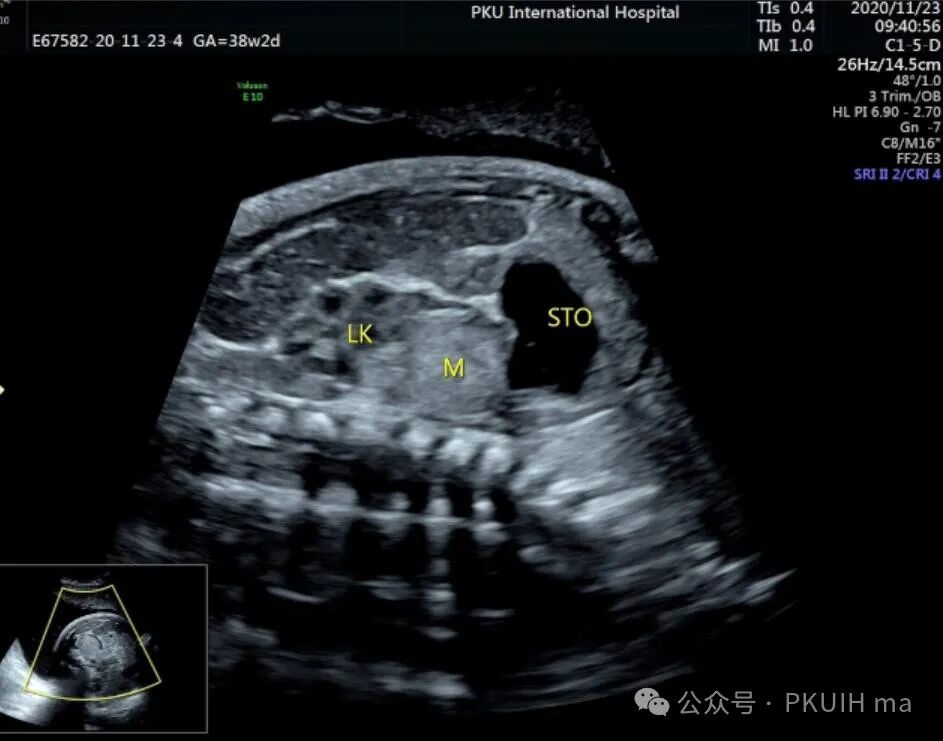

神经母细胞瘤是儿童时期最常见的肿瘤之一,其发病率为1/10,000 -30,000儿童。神经母细胞瘤可在妊娠晚期被诊断出来。产前诊断的肿瘤往往较小,90%涉及肾上腺。囊性和实性区域是典型的,可伴有出血和坏死。囊性病变预后较好。神经母细胞瘤可有微钙化,伴有声影、完整包膜和造成肾脏下移。这些肿瘤可能出现在颈部、胸部或腹部椎旁交感神经节的其他部位。引起气道压迫的宫内病变已有报道。肾上腺肿块伴肝肿大提示神经母细胞瘤的诊断。

上图是一例在孕晚期发现的肾上腺占位,生后病理证实为神经母细胞瘤的患儿,生后及时做了治疗预后非常好,目前宝宝各项指标都很好。

这几年我们在孕晚期发现有3例神经母细胞瘤胎儿,预后都很好。在孕晚期超声中建议常规扫查下胎儿双肾区